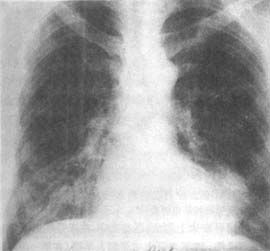

青年心肌梗死X線檢查①急性期和遠期病死率低;

②近期與遠期的預後較好。50例40歲以下心肌梗死患者急性期後生存47例,病後半年內死亡2例,其餘全部復工,無一例喪失勞動力。大部分患者在病後1年內即能上班,且可勝任病前的勞動量。